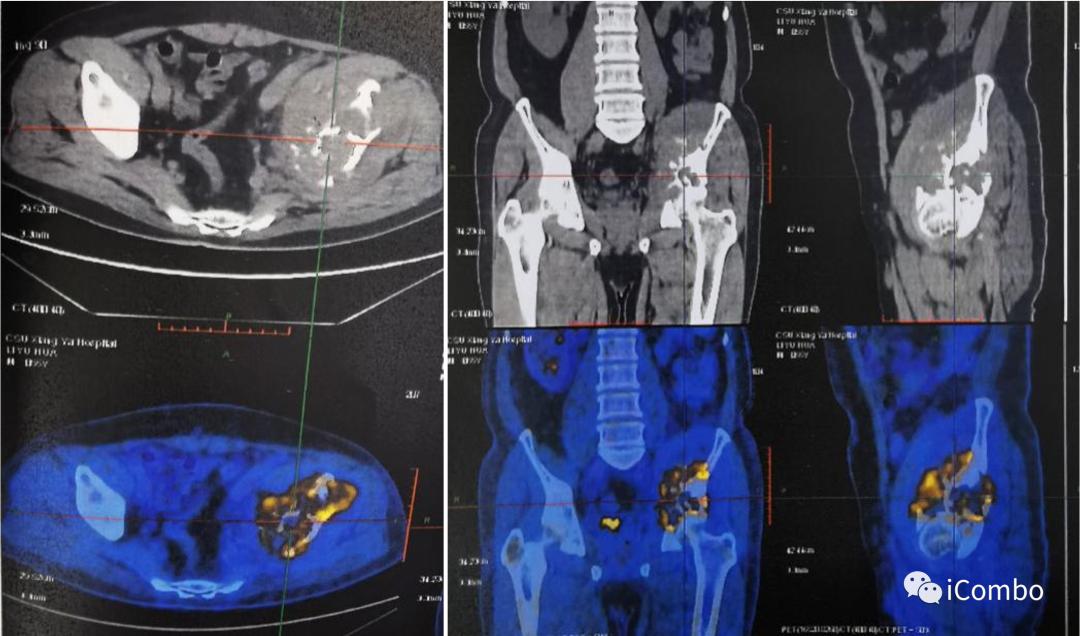

2018.9左髂骨疼痛,穿刺确诊左髂骨转移

2019.6 肿瘤进展,骨痛加剧

1、2019-7-22泌尿肿瘤多学科会诊,考虑肿物过于巨大,局部联合治疗,更换药物给予二线靶向联合免疫,肿物缩小后再联合局部放疗。

2、2019-8-9患者对药物耐受性不佳,疼痛较前加重,蛋白尿增加至3+,血RBC:2.56×10E12/L,Hb:80g/L,予以对症处理。2019-8-23:血RBC:3.09×10E19/L,Hb:87g/L,局部消融治疗。